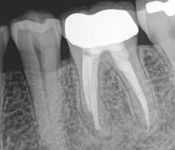

Pictured: Preoperative, Retreatment, Apicoectomy

and 5 Year Recall

Our patient required root canal retreatment. After an apicoectomy, the removal of the root tip and the infected tissue, there was complete bone healing in the 5 year recall.